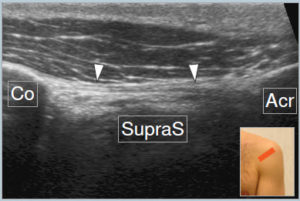

shoulder-9

← MSK ULTRASOUND – SHOULDER